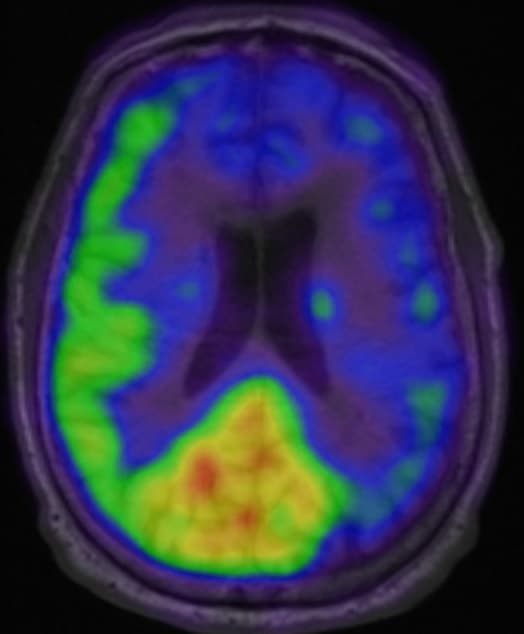

Den mest valide metode til påvisning af cerebral hypoperfusion og CVR er en 15O-H2O-PET [14], hvor der foretages en baselineskanning i hvile og en skanning 20 minutter efter infusion med acetazolamid eller under inhalation af CO2, som medfører dilatation af de cerebrale kar, og dermed gør det muligt at bestemme hjernens perfusion ved induceret hyperæmi. Ved at sammenligne hvileskanningen med skanningen, der blev foretaget efter indgift af acetazolamid eller CO2 fås et mål for CVR. En lav eller endda negativ CVR (såkaldt steal) indikerer, at den vaskulære reserve er opbrugt [16], hvilket betegnes som hæmodynamisk svigt og øger risikoen for apopleksi pga. nedsat blodgennemstrømning fokalt i hjernen i forsyningsområdet for det afficerede kar.

15O-H2O-PET/MR-skanning viser nedsat perfusion i venstre hemisfære efter indgift af acetazolamid.